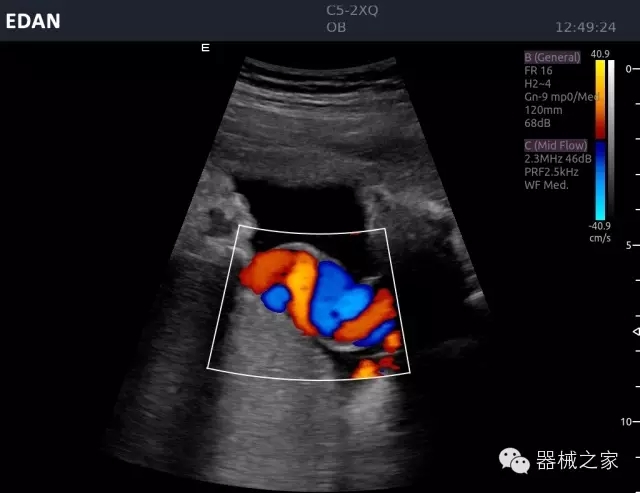

品牌:理邦儀器(EDAN)

經(jīng)典產(chǎn)品:Acclarix AX8

臨床圖片賞析

睪丸低速血流

臍帶血流

頸動脈頻譜